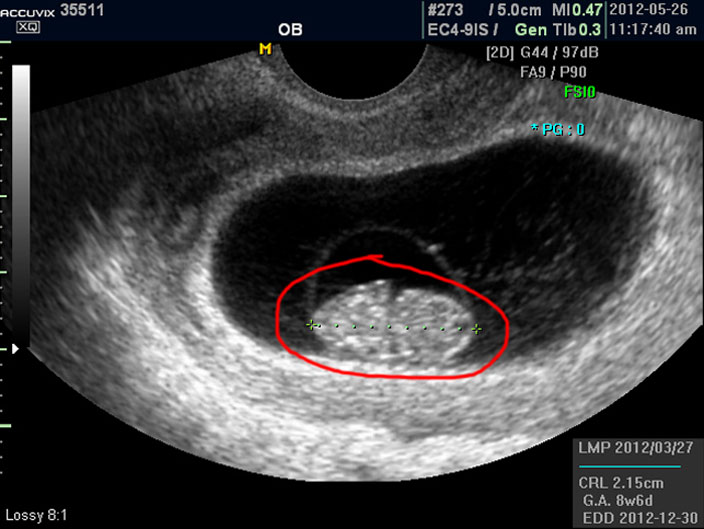

태아의 크기는 우측 하단에 실제 크기가 나와 있지만 아래 사진에서 빨갛게 표시한 부분의 안에 보이는 눈금이 1cm입니다.

이런 기준이나 지표들이 표시되는 것은 초음파 장비마다 조금씩 차이가 있고 위치도 다르지만 대개 비슷한 모양이라 한가지를 알면 다른 기종에서도 감상에 그리 어렵지는 않습니다.

마지막으로 볼 것은 아기의 정보를 나타내 주는 수치들입니다.

으로 우측의 LMP라고 된 숫자는 산모의 최종 월경일이며 이는 초음파로 판단한 것이 아니라 산모의 진술을 바탕으로 한 것인데 이것이 중요한 이유는 초음파는 그저 크기만을 알아 내는 것이라 임신 주수에 걸맞게 잘 자라는지 판단하려면 월경 주기를 알아야 하기 때문입니다.

그 아래 보이는 CRL이라는 것은 Crown Rump Length의 약자로 아기의 머리부터 엉덩이 끝까지의 실제 길이입니다.

임신 12주 내지 13주 정도의 초반기의 아기 발육은 주로 아기의 전체 크기를 가지고 판단하는데 엉덩이까지 체크하는 이유는 흔히 태아는 다리를 구부리고 있기 때문에 성인 인간처럼 머리끝부터 발끝까지 실제 키를 재기가 어렵기 때문입니다.

그 아래 GA 는 Gestational Age의 약자로 우리말로는 태령이라고 하며 초음파의 CRL을 기준으로 했을 때 어느 시기의 태아의 수준인가를 말해 주는 것입니다.

따라서 산모의 LMP를 기준으로 한 태령과 초음파로 측정한 태아의 태령은 1주 정도의 오차로 비슷한 것이 정상이며 간혹 최종 월경일을 틀리게 알고 있거나 아기의 발육에 문제가 있을 때는 큰 차이가 날 수 있습니다.

맨 아래의 EDD는 Estimated Due Date의 약자로 출산 예정일을 말하는데 초음파를 기준으로 했을 때 이정도 시기가 출산 예정일이 될 것이라는 계산입니다.

그러나 이것은 어디까지나 초음파로 예상한 시기이며 실제 출산은 앞뒤로 2주 씩의 오차가 있을 수 있습니다.